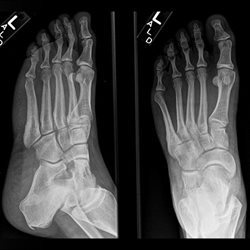

Various foot cases